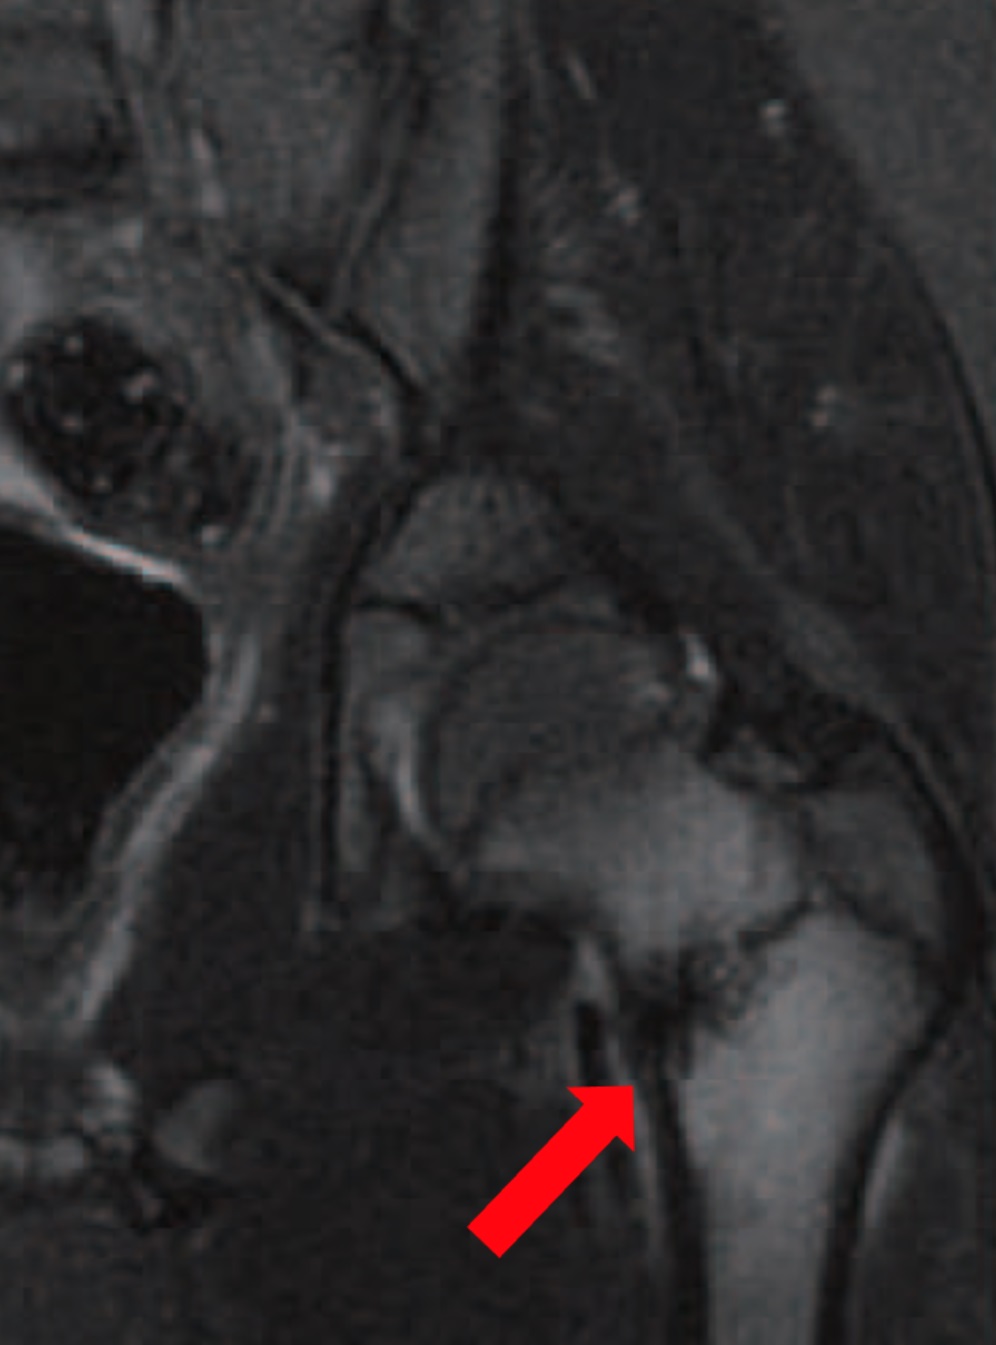

La patologia intrarticolare dell’anca è assai vasta e può comprendere le alterazioni morfologiche del profilo articolare, ai corpi mobili, alle stress fracture (fig. 2), all’artrosi.

L’equipe della Chirurgia Ortopedica Ricostruttiva Tecniche Innovative ha messo a punto un percorso diagnostico-terapeutico dedicato ai pazienti affetti da coxalgia. L’iter prevede visita specialistica e l’integrazione con esami strumentali mirati (ecografia dinamica (fig. 5), radiografie con proiezioni specifiche, ricostruzioni tridimensionali TC (fig. 6), RMN ad alto campo, test con anestetico intra o extra-articolare).